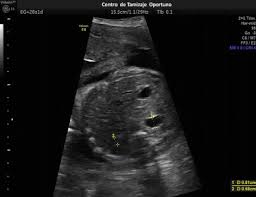

Que significa lf en un ultrasonido. Se consideró como biometría fetal estándar a la medición del diámetro biparietal DBP circunferencia cefálica CC longitud del fémur LF y circunferencia abdominal CA. CC en español corresponde al perímetro de la cabeza siempre en milímetros. EPF en español estimación del peso del feto en gramos.

Mide la longitud del fémur el hueso del muslo y se expresa en milímetros. Por sunnyfunny Mié Oct 08 2008 859 pm. LF en español es longitud del fémur expresada en milímetros.

Que significa dbp en. Permite establecer la fecha aproximada de la concepción y la fecha probable del parto. SEGUNDO TRIMESTRE 14 a 28 semanas En el segundo trimestre al igual que en el tercero se aceptan como mínimos requerimientos para cálculo de la edad gestacional la medición de DBP CA CC LF.

COLUMNA CORAZON DE 4 CAMARAS. Y biometría fetal secundaria a la medición del diámetro cerebeloso transverso DCT longitud renal LR y longitud del pie LP. Diámetro biparietal de un lado a otro de la cabeza expresado en milímetros.